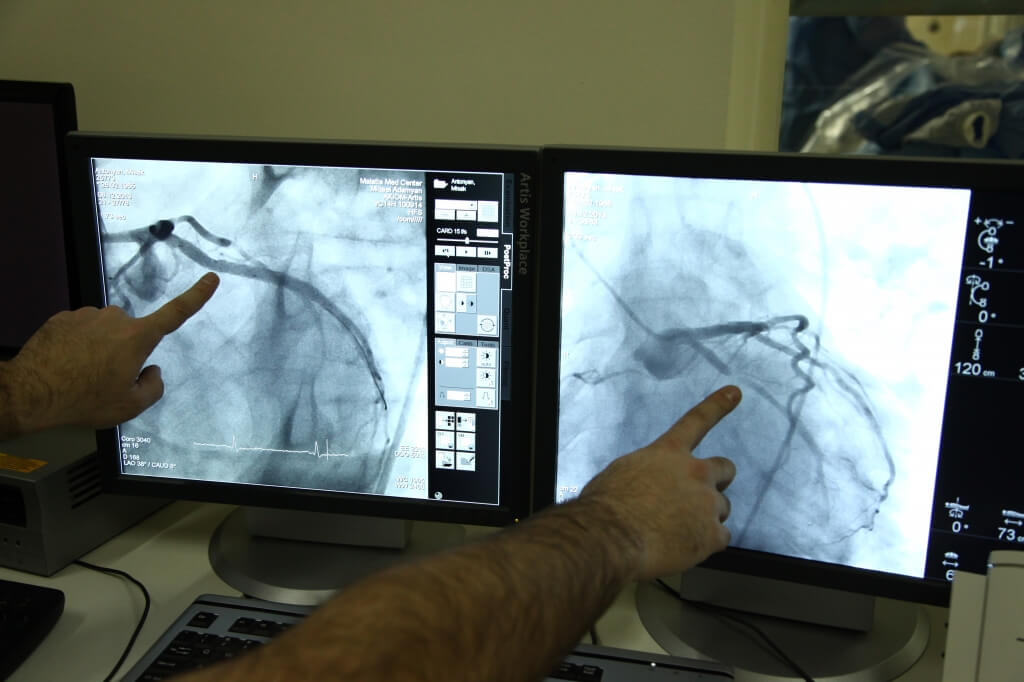

При проведении аортографии, которая включает исследование грудного и брюшного отделов аорты с использованием контрастного вещества, выявляются признаки атеросклеротического поражения: расширение отдельных участков аорты, отложения кальция, аневризмы, а также удлинение и уплотнение стенок сосуда. Для оценки состояния коронарных сосудов выполняется коронарография, представляющая собой эндоваскулярное исследование.